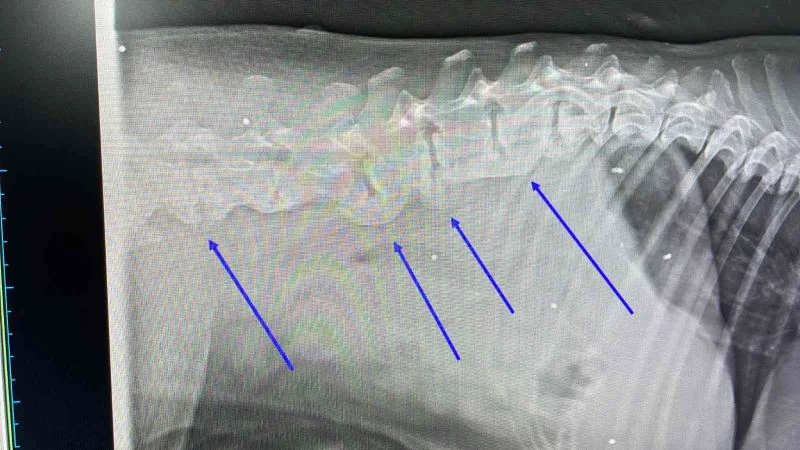

Muğla’nın Bodrum ilçesinde trafik kazası sonucu yaralanan köpeğin çekilen röntgen filminde, daha önce tüfekle vurulduğu ve vücudundaki saçmalarla yaşadığı ortaya çıktı.

Araç çarpması nedeniyle kalçasında kırık olan köpeğin vücudunda onlarca saçmaya rastlandı. Saçmalar, hayvanın daha önce tüfekle vurulduğunu ve vücudunda saçmalarla yaşadığını ortaya çıkardı. Köpeğin ne zaman vurulup ne zamandan beri vücudunda saçmalarla yaşadığı bilinmiyor. Hayvanın tedavisinin özel bir veteriner kliniğinde sürdüğü öğrenildi.